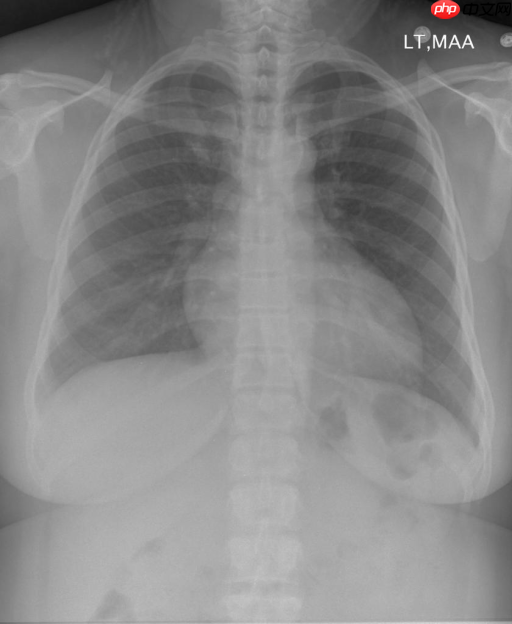

印第安纳大学胸部 X 射线集合 (IU X 射线) 是一组胸部 X 射线图像及其相应的诊断报告。该数据集包含 7,470 对图像和报告(6470:500:500)。 每个报告由以下部分组成:印象、发现、标签、比较和指示。平均每张图像关联2.2个标签,5.7个句子,每个句子包含6.5个单词。

Impression + Finding: bleu = [0.427, 0.3008, 0.2153, 0.155], meteor = 0.1799, rouge = 0.3459, cider = 0.1384| 图片-CXR2230_IM-0831-1001 |

Findings

mediastinal contours are normal .

heart size is upper limits of normal .

lungs are clear .

there is no pneumothorax or large pleural effusion .

no bony abnormality.

the heart size is normal .

the lungs are clear .

there is no pneumothorax or pleural effusion .

there are no focal areas of consolidation .

no pneumothorax .

no pleural effusion .

Impression

no acute cardiopulmonary abnormality

根据生成结果,可以发现生成的结果是具有一定的医学语义的。